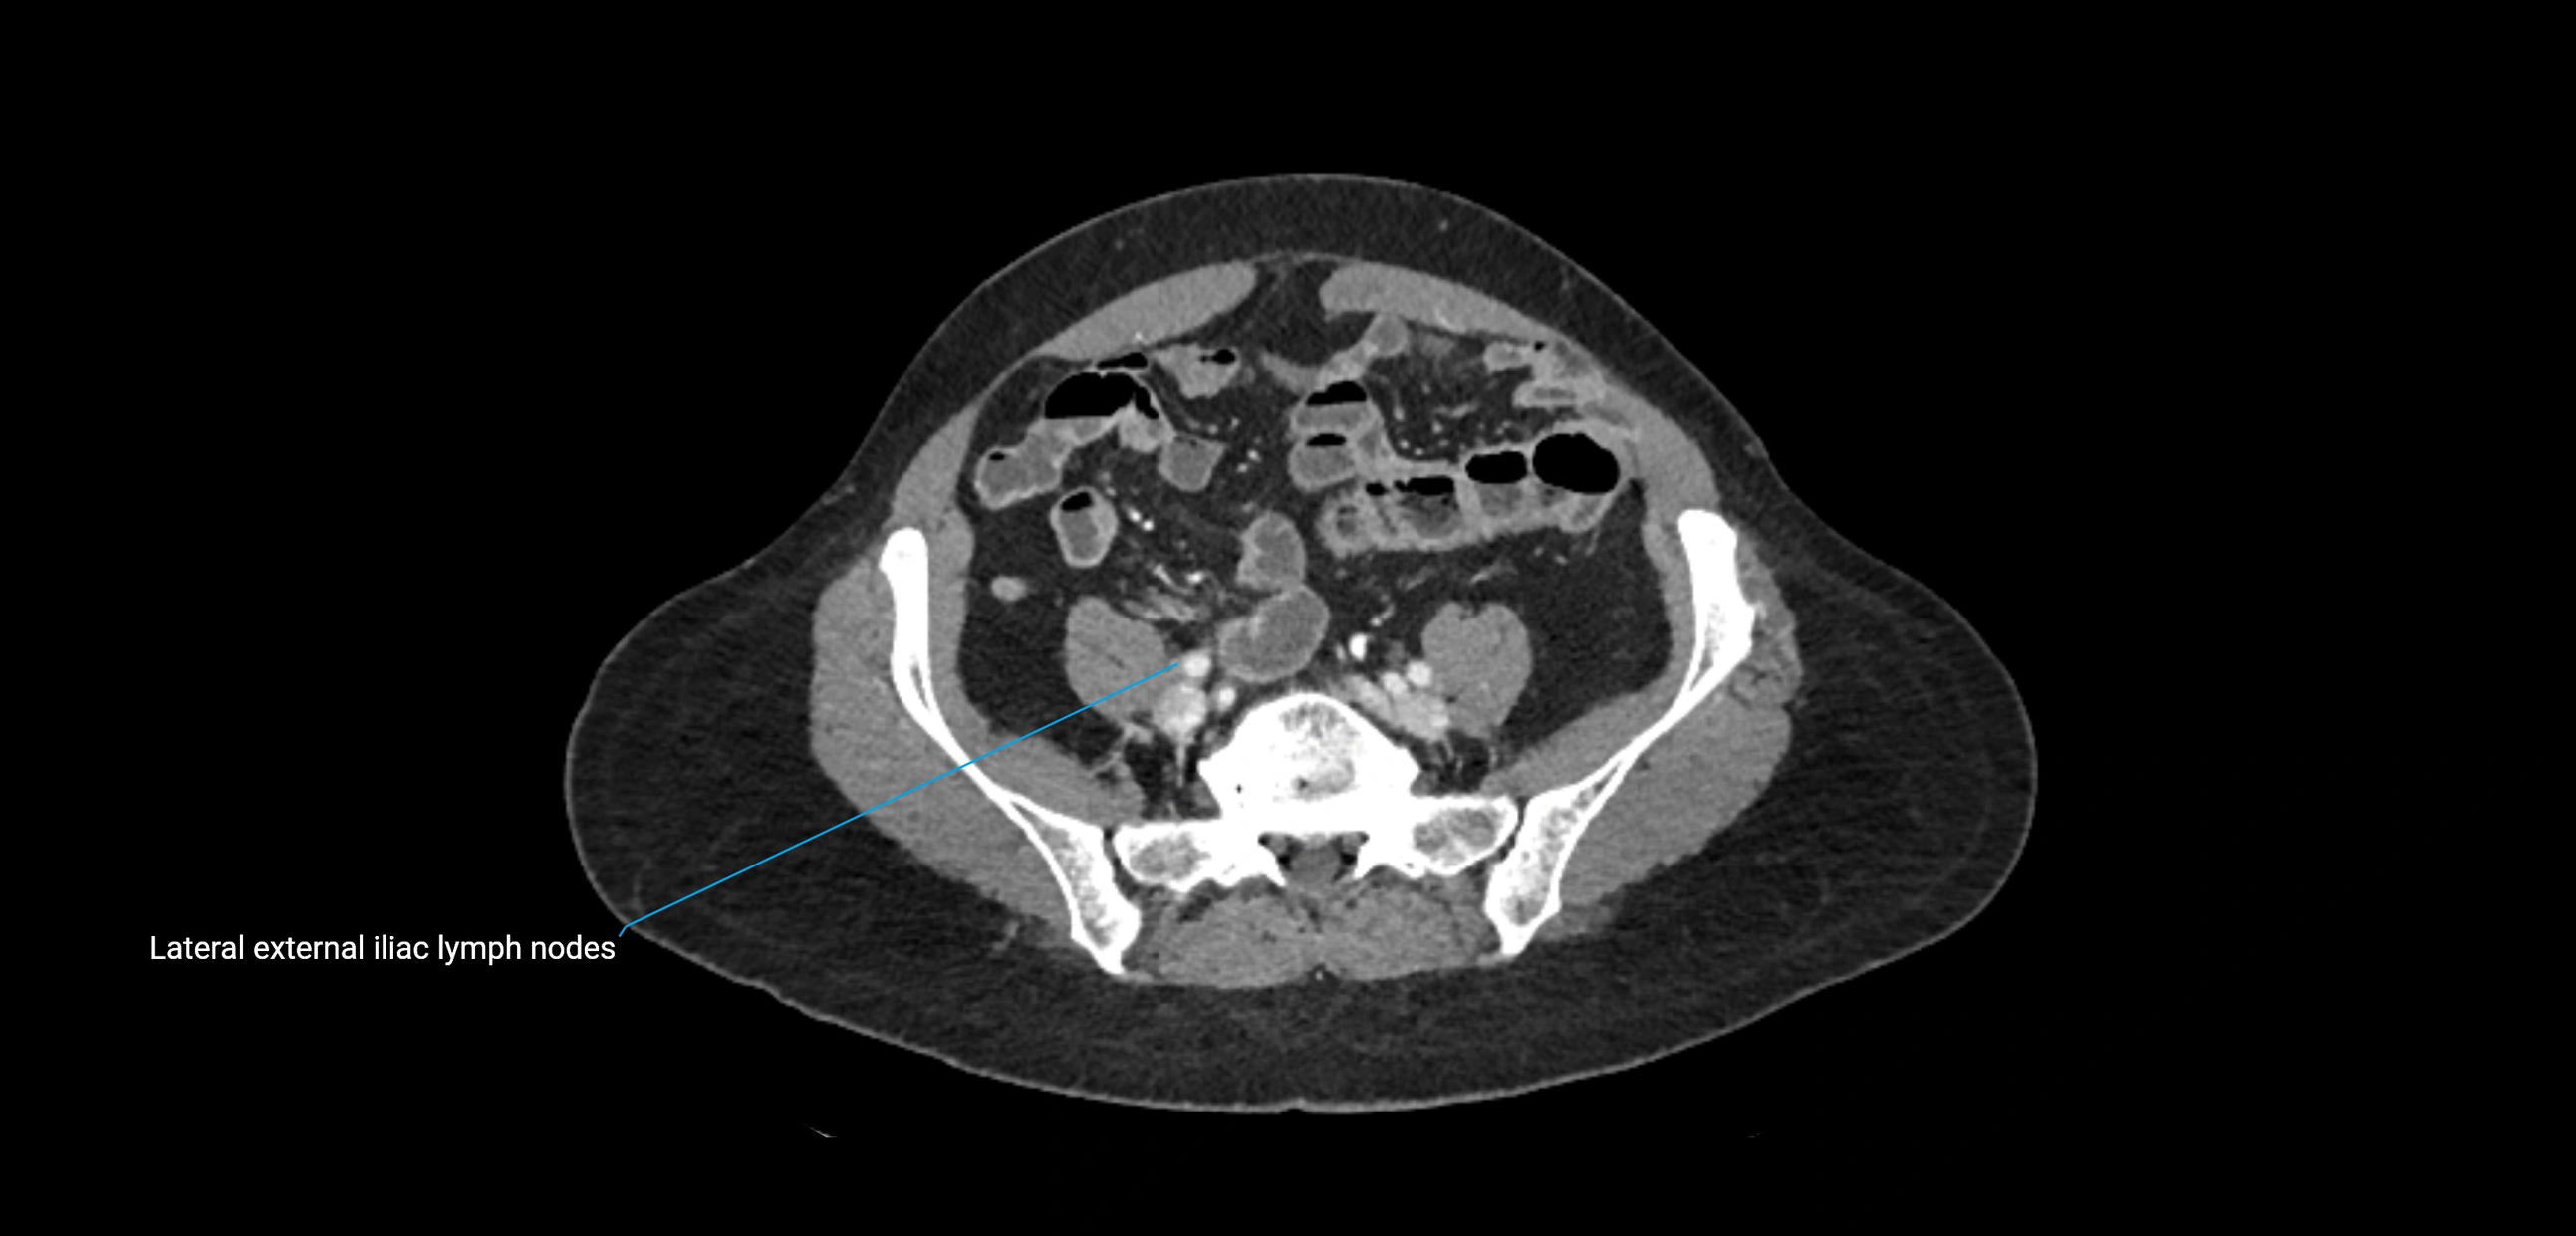

CT image

image